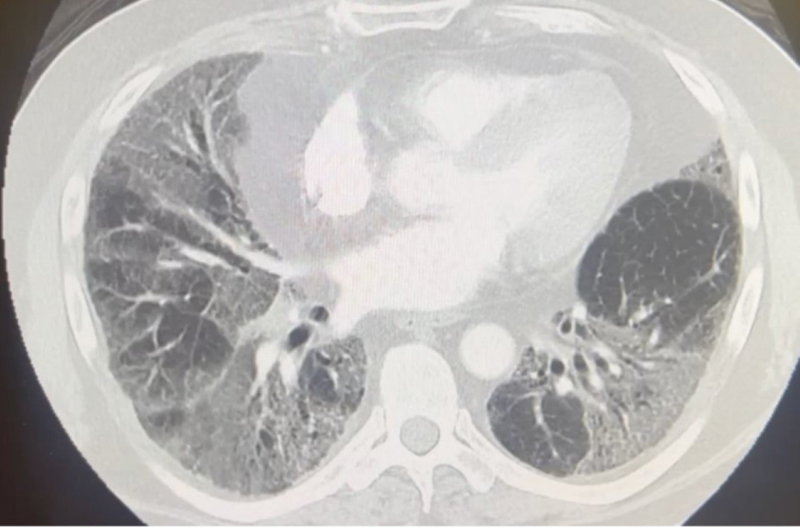

Figure 3

Figure 3. Computed tomography with angiography of the chest showed bilateral multifocal ground glass opacities and increased septal thickening with underlying lung fibrosis.